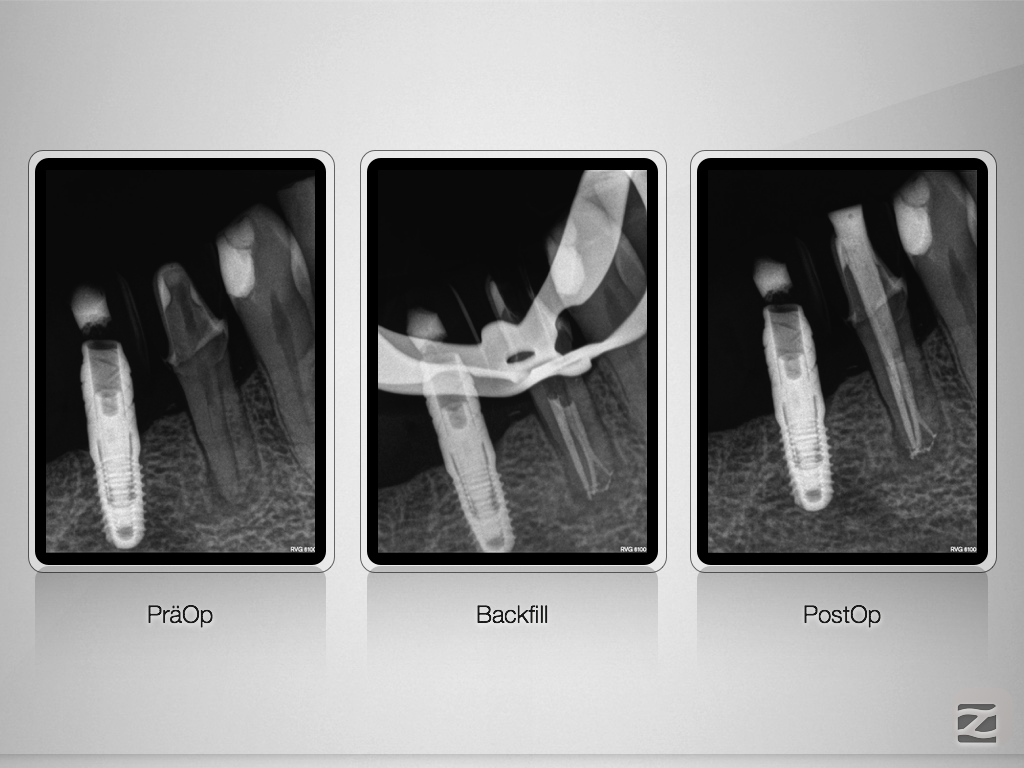

44D.009

Prämolar mit Hürden